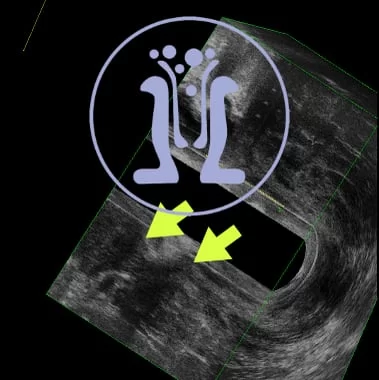

Ασθενής, 64 ετών, με ιστορικό παροχέτευσης περιεδρικού αποστήματος προ 2 εβδομάδες. Ο ασθενής ανέφερε επίσης έναρξη δυσκοιλιότητας και παρουσία αίματος στα κόπρανα από 3 μήνου. Το ενδοπρωκτικό υπερηχογράφημα έδειξε, από το δέρμα μέχρι τα στα 5-46 mm πάνω από το άνω όριο των σφιγκτήρων, διηθητική χωροκατακτητική εξεργασία πάχους 21 mm. Επιπροσθέτως, αυτή επεκτείνεται σαφώς στο περιορθικό λίπος και στο επίπεδο του πρωκτού διηθεί τον έξω σφιγκτήρα. Κάτω και στην 1η ώρα του πρωκτού ανευρέθηκε παροχετευμένο περιεδρικό απόστημα στο υπόβαθρο της διηθητικής επεξεργασίας. Συνεστήθη λήψη βιοψιών της εξεργασίας και κατόπιν ογκολογική συνεκτίμηση προ του χειρουργείου.